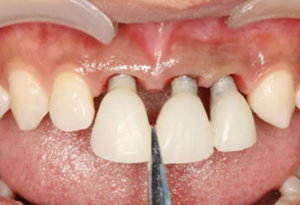

圖15 調(diào)整臨時修復(fù)體外形

圖16 軟組織成形后口內(nèi)像

(3)軟組織成形。術(shù)后4個月復(fù)查,臨時修復(fù)體完好,軟組織色粉、 質(zhì)韌、點彩清晰,齦緣位置基本穩(wěn)定,齦乳頭區(qū)可見三角間隙。此后1個月內(nèi),先后2次取下臨時冠,用樹脂調(diào)整修復(fù)體頸部外形,進行軟組織成形。 術(shù)后6個月復(fù)查,軟組織形態(tài)滿意、位置穩(wěn)定,進行最終修復(fù)。